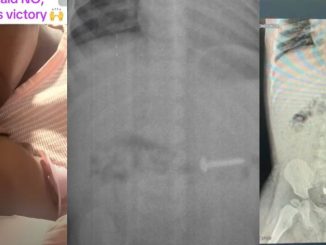

A mother has recounted a miraculous experience involving her one-year-old daughter who accidentally swallowed a nail just a week after her first birthday. According to her, doctors confirmed the object was stuck in the child’s